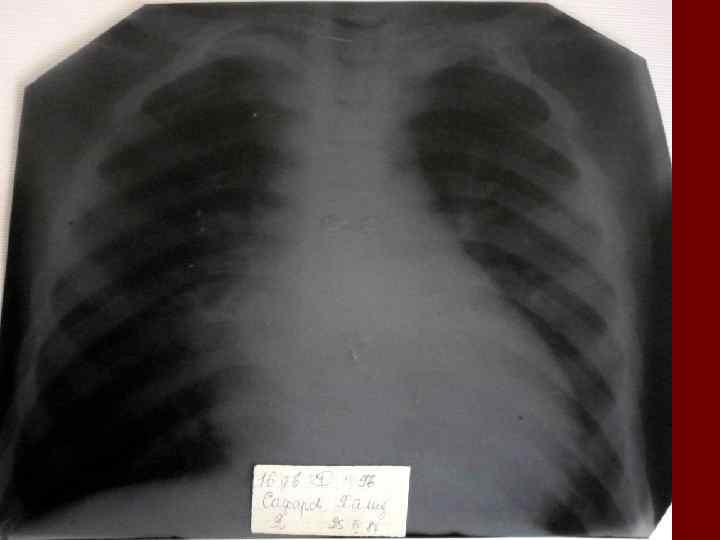

Долевая пневмония характеризуется лобарным пневмоническим инфильтратом. Крупозная ( пневмококковая) пневмония диагностируется прежде всего по клиническим данным. Крупозная пневмония сохраняет свою типичную картину пневмококковой пневмонии: острое начало с характерными клиническими данными, циклическое течение, несклонность к деструкции, гомогенной и лобарной инфильтративной тенью при рентгенологическом исследовании. Вместе с тем, широкое использование антибиотиков способствовало значительному снижению числа крупозных пневмоний у детей. Интерстициальная – редкая форма пневмоний, при которой оказывается поражен прежде всего интерстиций. Как правило, интерстициальная пневмония обусловлена вирусами, пневмоцистами, внутриклеточными микроорганизмами и грибами.

Морфологическую форму пневмонии определяют по клинико – рентгенологическим данным: выделяют очаговую, очагово – сливную, долевую ( крупозную), сегментарную и интерстициальную пневмонии. Очаговая – наиболее распространенная форма. Пневмонические очаги чаще бывают размером 1 см и более. Очагово – сливная – инфильтративные изменения в нескольких сегментах или во всей доле легкого, на фоне которых могут быть видны более плотные участки инфильтрации и/или полости деструкции. Сегментарная – в процесс вовлекается весь сегмент, который, как правило, находится в состоянии гиповентиляции, ателектаза. Морфологическая картина воспаления при очаговых и сегментарных пневмониях связана с первичным инфекционным воспалением в бронхах, что дает основание отнести эти варианты поражения легочной ткани к бронхопневмониям, нередко сопровождающихся бронхообструктивным или бронхообтурационным синдромами. В настоящее время данный тип пневмоний у детей встречается наиболее часто.